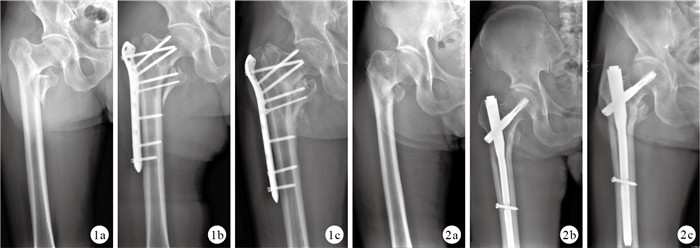

PFNA組切口長度、手術時間、術中出血量及下地活動時間均顯著優于LCP組,但術中透視次數顯著多于LCP組,比較差異均有統計學意義(P<0.05);兩組總出血量比較,差異無統計學意義(t=—1.686,P=0.096)。見表 1。兩組患者均獲隨訪,PFNA組隨訪時間12~24個月,平均18.3個月;LCP組15~30個月,平均19.1個月。X線片復查示,PFNA組骨折均愈合,愈合時間(12.667±2.527)周。LCP組1例骨折未愈合,與患者術后3周即下地部分負重行走,導致骨折移位有關,行人工全髖關節置換;其余患者骨折均愈合,愈合時間(13.364±1.194)周。兩組骨折愈合時間比較,差異無統計學意義(t=—1.443,P=0.154)。見圖 1、2。術后12個月PFNA組Harris評分為(84.611±7.076)分,LCP組為(81.785±7.500)分,兩組比較差異無統計學意義(t=1.626,P=0.109)。